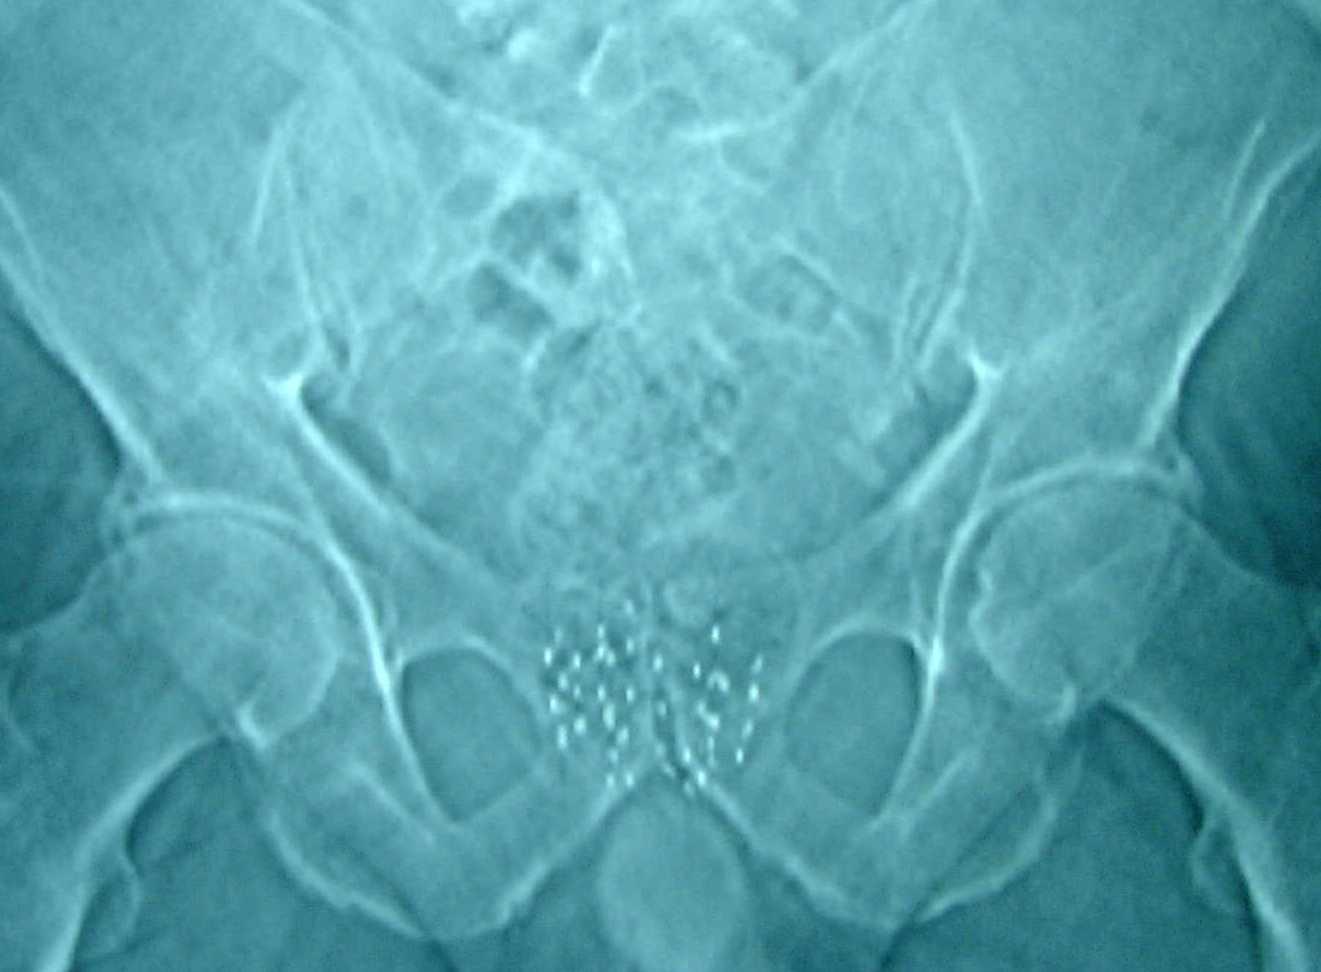

Röntgenfoto van het bekken met Jodium 125 zaadjes

Het hulsje van het zaadje is gemaakt van titanium. De zaadjes zijn zo groot als een rijstkorrel. In het hulsje zit het radioactieve Jodium 125 opgesloten. Het radioactieve Jodium 125 geeft de straling af.

De straling neemt geleidelijk af en na 60 dagen is de straling met de helft afgenomen. Op een gegeven moment is de straling uitgewerkt. De zaadjes worden niet uit de prostaat gehaald en blijven voor de rest van uw leven in de prostaat zitten, u voelt daar niets van.

In de hele prostaat worden zaadjes geplaatst. Het inbrengen van de zaadjes gebeurt op de operatiekamer. Voor het plaatsen van de zaadjes wordt u opgenomen in Amsterdam UMC locatie AMC.